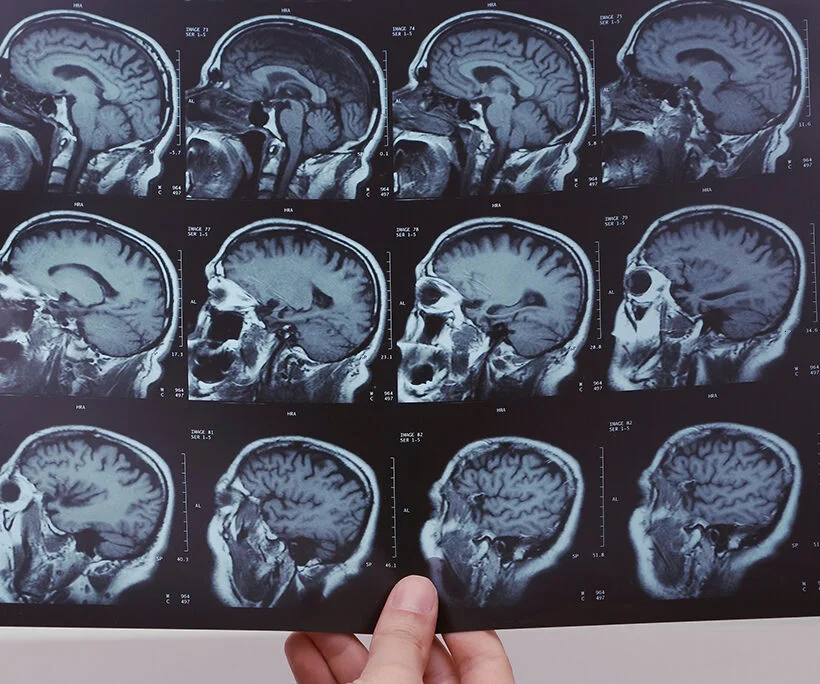

Childhood brain cancer is the leading cause of cancer-related death in children and adolescents, comprising over 16 percent of pediatric cancer diagnoses and encompassing over 100 rare and complex tumor subtypes. SPARC has partnered with leading institutions and a dedicated anonymous donor to support an integrated, global program that spans molecular research, therapeutic development, and cross-sector collaboration to accelerate innovation, address systemic funding gaps, and improve outcomes for affected children and their families.

Glioblastoma multiforme is the most aggressive and deadly form of brain cancer, with limited treatment options and a median survival rate of just over one year. SPARC has driven progress by identifying strategic funding opportunities, identifying opportunities to advance clinical trial innovation, and accelerating research aimed at improving outcomes.